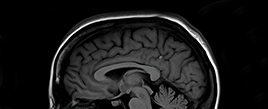

Brain & Spine Care

Our highly-trained neurosurgeons and neurologists treat all conditions of the brain and spine. With six hospitals in the Portland, OR and Vancouver, WA areas, we provide the highest-level care and convenience.

We understand how hard it can be to have or care for a loved one with a brain, spine or nervous system disorder or injury. That’s why we come alongside you and be your guide toward healing and recovery. Our hospitals offer the highest-level care with: